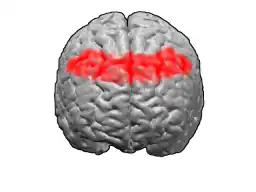

Image of brain with Brodmann area 8 shown in red | |

front view.

front view. -